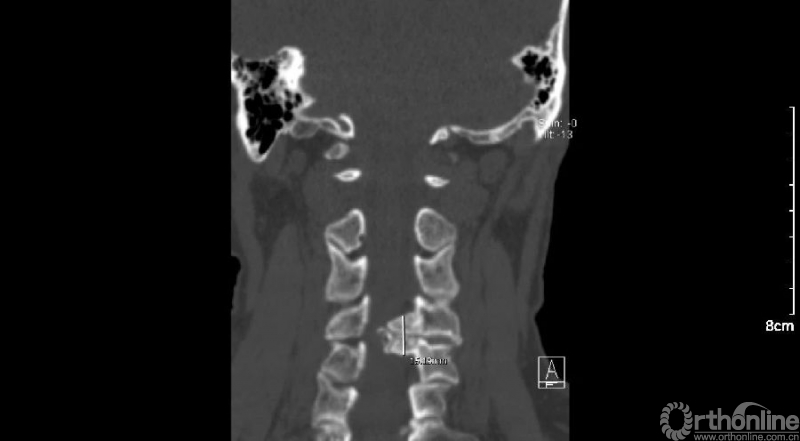

入院查体患者四肢肌张力高,双侧hoffman阳性。CT及MRI检查提示C4/5左侧关节突内缘有一巨大骨块(15mm*16mm),相应节段椎管严重狭窄。椎管内骨块的前端还有一游离骨块。

影像学资料